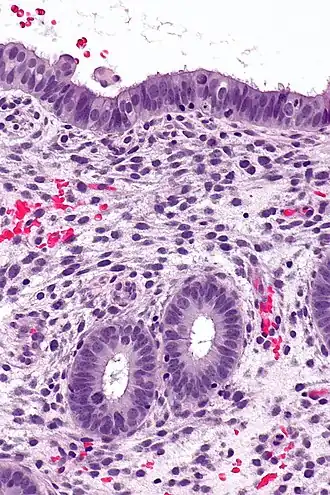

(A) proliferative endometrium (Left: HE × 400) and proliferative endometrial cells (Right: HE × 100)

(B) secretory endometrium (Left: HE × 10) and secretory endometrial cells (Right: HE × 10)

(C) atrophic endometrium (Left: HE × 10) and atrophic endometrial cells (Right: HE × 10)

(D) mixed endometrium (Left: HE × 10) and mixed endometrial cells (Right: HE × 10)

(E): endometrial atypical hyperplasia (Left: HE × 10) and endometrial atypical cells (Right: HE × 200)

(F) endometrial carcinoma (Left: HE × 400) and endometrial cancer cells (Right: HE × 400).